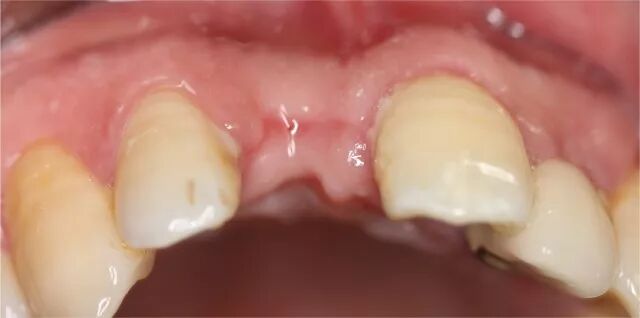

外傷拔牙后三個月

拔牙4個月后